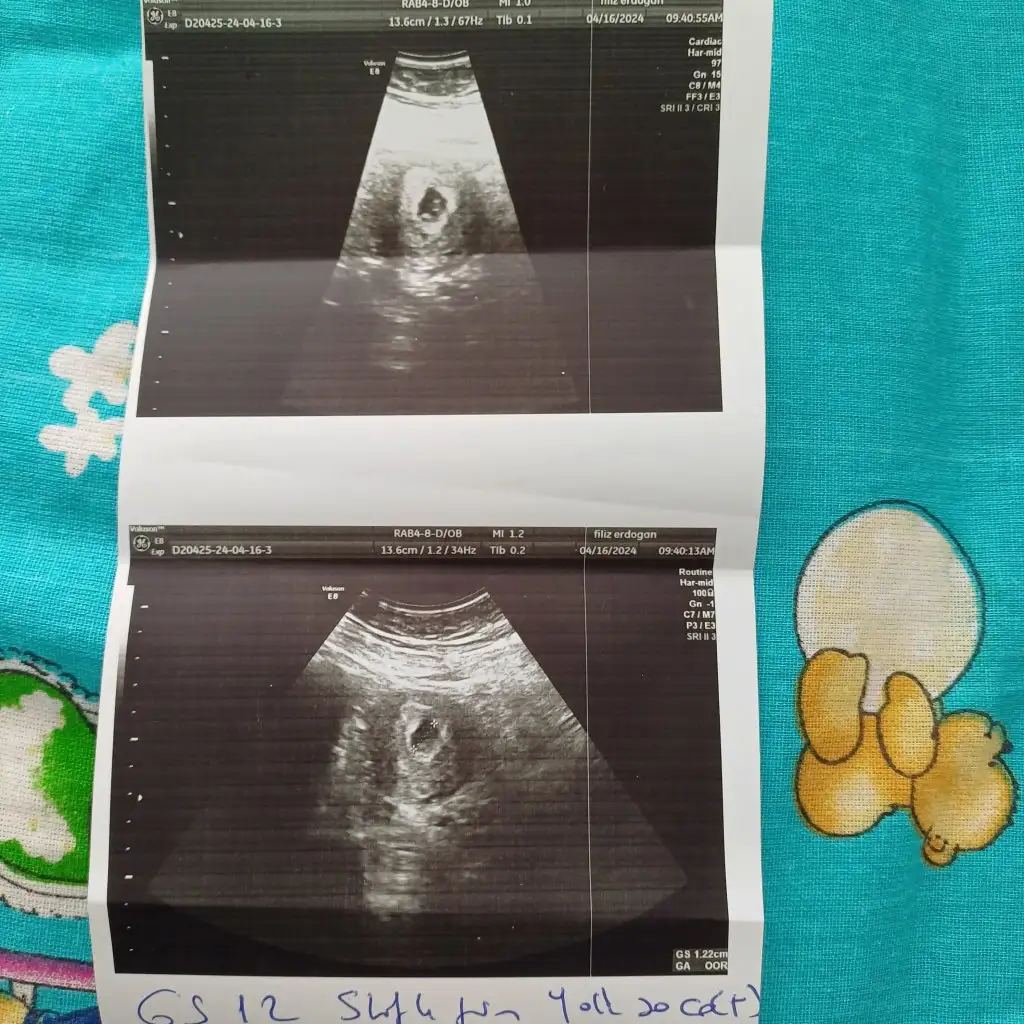

Hayir yspilmadi cnm isdemedi doktorumuz ilk denene 5.gun 4bb dondurulmus embiryo transferi olmusdum 26 martdaBak canım bana gittiğim özel prof dedi bu ultrason cihazını hareket ettirdikce onun görüntüsü değişir benim sonraki ultrason resmim yamuk yumuk birşey sen bol bol su iç dinlen bak bebeğin görünmüş bebeğe genetik pgt yapıldı mı

Tekrar kontrolü ne zamana söyledi sen dinlen kalkma iş yapma ben yapmadım hep yattım sırtım agirmisti okadar yattım hala leke devam ediyor ama bebislerim iyi elhamdülillah hepimiz sana dua edeceğiz rabbim bebeğini sana bağışlasın hemen kötüleri çağırma ben hep kendime dedim ki eğer bizim evimizde rızkı varsa yasayacaksa buna kimse engel olamaz ama ömrü yoksa yasamayacaksa biz ne yapabiliriz ki ben 9 tane kaybetmişim ne yapabildim hiç birşey sadece sabır dua tevekkülHayir yspilmadi cnm isdemedi doktorumuz ilk denene 5.gun 4bb dondurulmus embiryo transferi olmusdum 26 martda

Haftaya persembe gitcezTekrar kontrolü ne zamana söyledi sen dinlen kalkma iş yapma ben yapmadım hep yattım sırtım agirmisti okadar yattım hala leke devam ediyor ama bebislerim iyi elhamdülillah hepimiz sana dua edeceğiz rabbim bebeğini sana bağışlasın hemen kötüleri çağırma ben hep kendime dedim ki eğer bizim evimizde rızkı varsa yasayacaksa buna kimse engel olamaz ama ömrü yoksa yasamayacaksa biz ne yapabiliriz ki ben 9 tane kaybetmişim ne yapabildim hiç birşey sadece sabır dua tevekkül